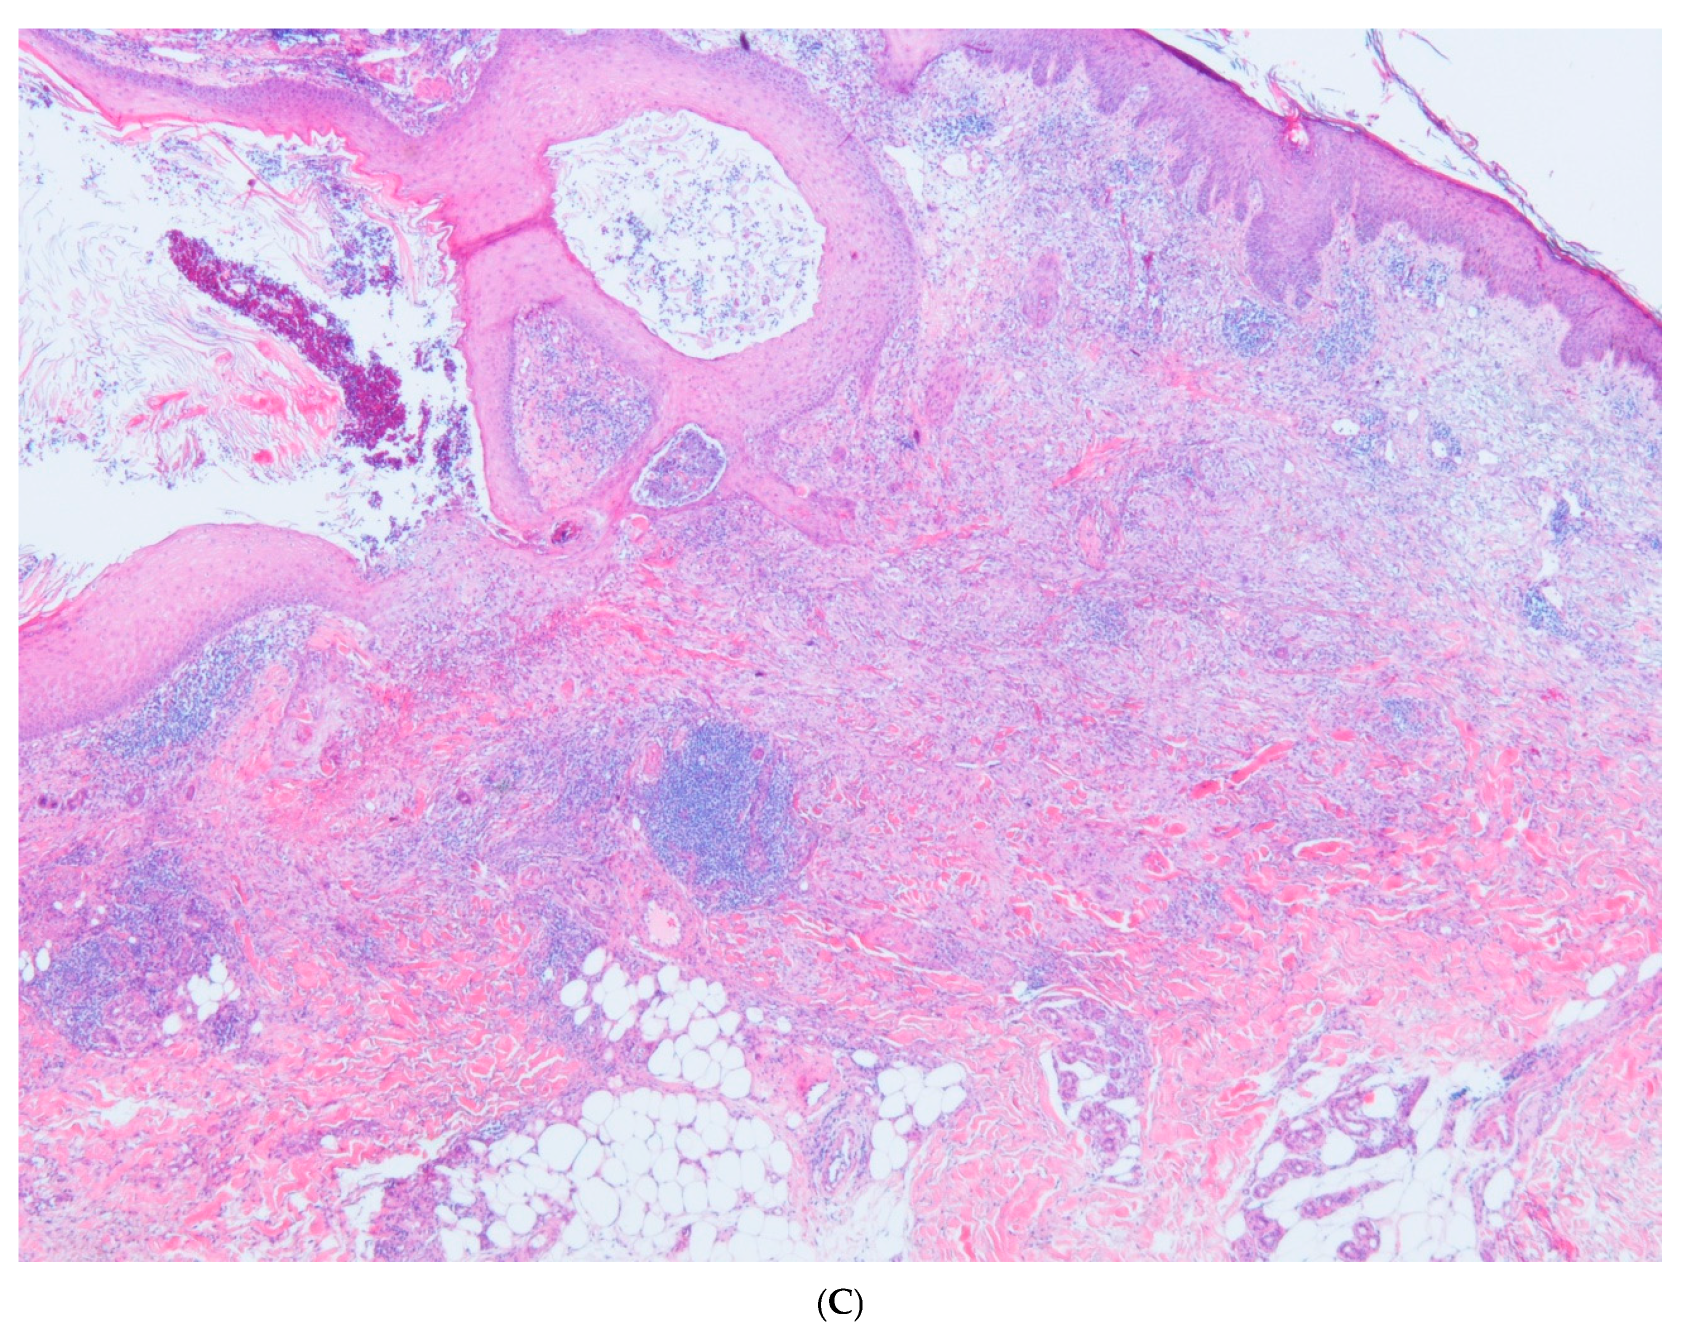

Perforating Granuloma Annulare with Cysts and Comedones

2. Case Report